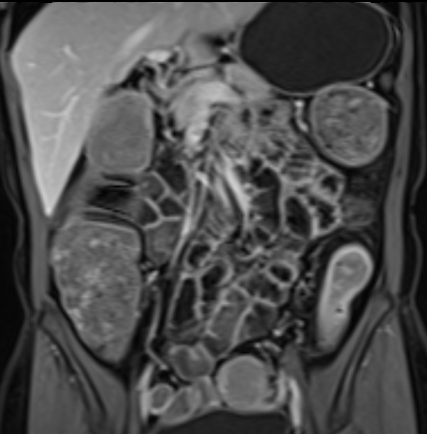

Bệnh nhân nữ 48 tuổi, đang điều trị bằng thuốc kháng TNF, được chỉ định nội soi đại tràng.

Phát hiện hẹp lòng ruột ở đại tràng sigma, không thể vượt qua được khi nội soi.

MR-enterography được thực hiện để đánh giá mức độ lan rộng của chỗ hẹp.

Cuộn qua các hình ảnh.

Ruột non bình thường, nhưng ghi nhận các đoạn hẹp ở đại tràng xuống và đại tràng ngang.

Cả hai đoạn hẹp đều có thành ruột dày đến 8 mm và ngấm thuốc rõ rệt theo kiểu niêm mạc ở đại tràng xuống và kiểu phân lớp ở đại tràng ngang.

Giãn ruột trước chỗ hẹp được ghi nhận ở cả hai đoạn.

Do các chỗ hẹp này không hiện diện khi nội soi đại tràng trước khi điều trị kháng TNF, nhiều khả năng chúng đã hình thành trong quá trình điều trị.

Do đó, quyết định phẫu thuật cắt đại tràng gần toàn bộ với miệng nối hồi-sigma đã được đưa ra.